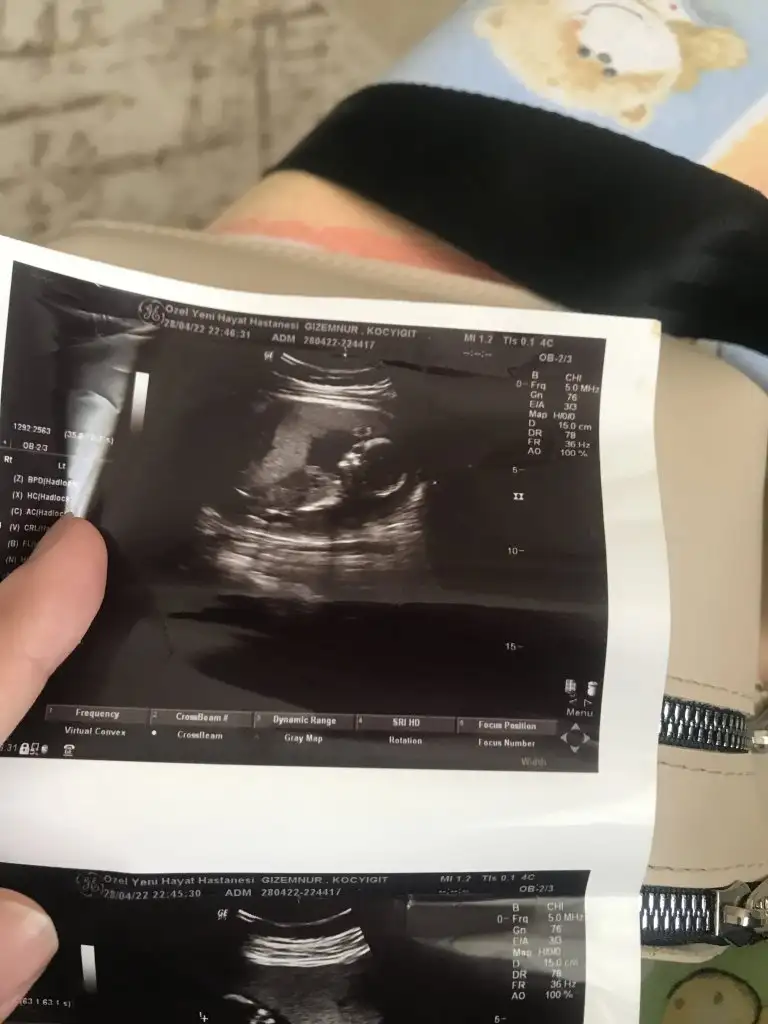

paşa gibi duruyor canımMerhaba 12+6 haftalık bizede yorum yapabilirmisinizPasha22

erken dönemde plastayı görmek çok zor ama genellikle bebek neredeyse plesanta orada oluyor.Bebeğin konumuna bakarak mı cinsiyet söylüyorsun yoksa plesanta nın konumumu

Ama ramzi teorisi ne göre plesantaya göre cinsiyet belirleniyor çünkü 6-7-8 haftalık ultrason görüntüsünde bebek sürekli yer değiştiriyo plesanta ilk haftalarda belli olmuyo ama dikkatli bakarsan ultrason da beyaz parlak bir alan var orasını plesanta olarak baz alıyoruzerken dönemde plastayı görmek çok zor ama genellikle bebek neredeyse plesanta orada oluyor.

evet ben de o şekilde yaparak tahmin yürütüyorum zaten. bazen parlak alan dahi görünmüyor. o yüzden kadınlarımıza ileriki haftalarda da görüntü gönderin tahmin edelim birlikte diyorum.Ama ramzi teorisi ne göre plesantaya göre cinsiyet belirleniyor çünkü 6-7-8 haftalık ultrason görüntüsünde bebek sürekli yer değiştiriyo plesanta ilk haftalarda belli olmuyo ama dikkatli bakarsan ultrason da beyaz parlak bir alan var orasını plesanta olarak baz alıyoruz